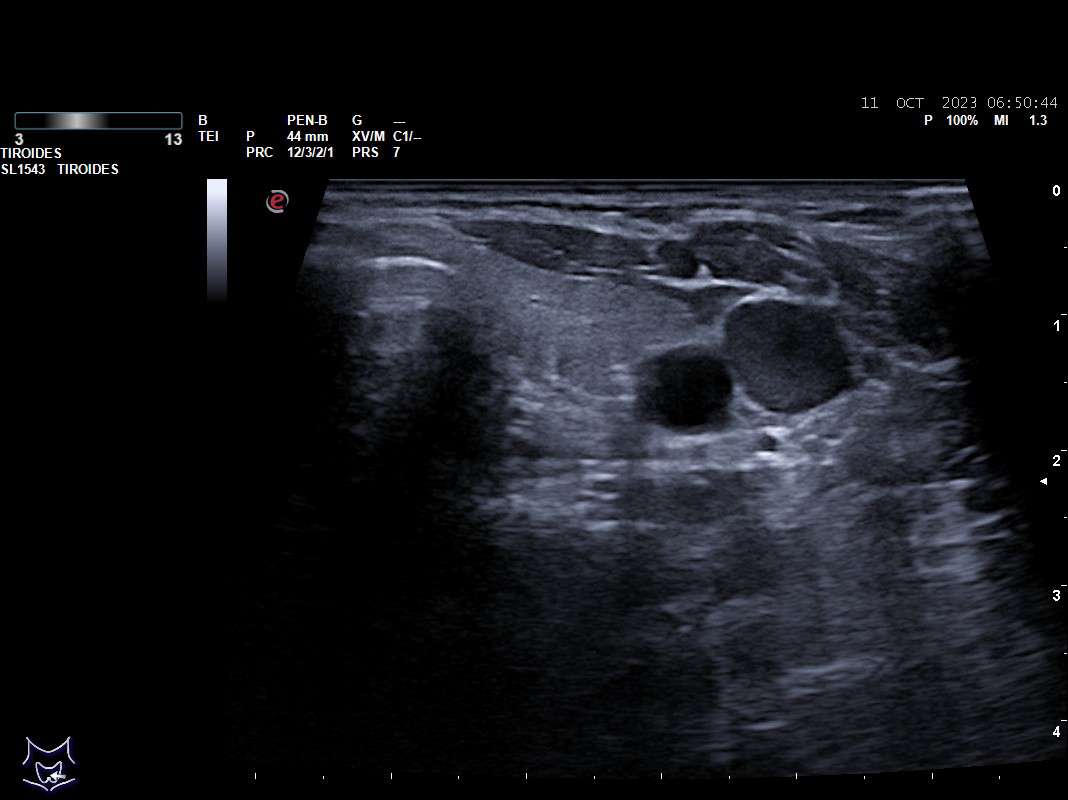

Hallazgos ecográficos: nódulos tiroideos subcentimétricos sin cambios, yugular interna izda con contenido discretamente hiperecogénico que no capta Doppler y colapsabilidad incompleta.